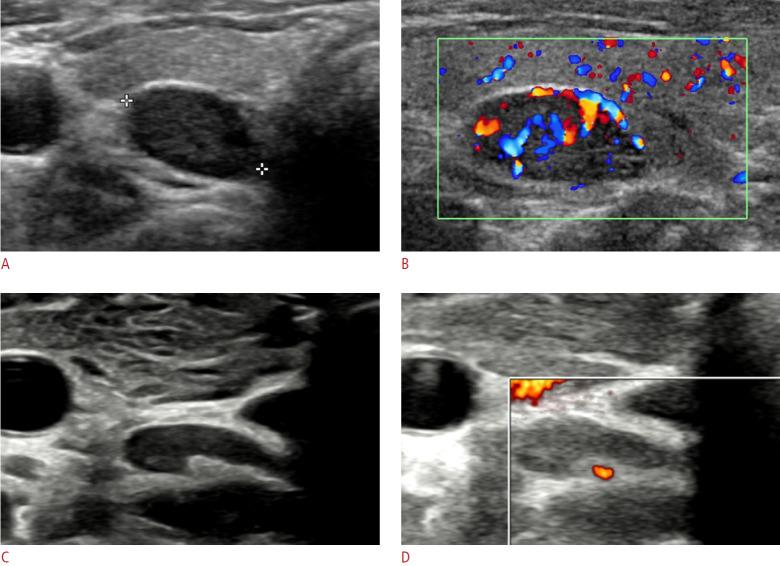

The parathyroid glands play a key role in maintaining calcium-phosphate homeostasis by secreting parathyroid hormone (PTH). Hyperparathyroidism, characterized by the inappropriate overproduction of PTH, is classified as primary, secondary, or tertiary according to its pathophysiology. Although diagnosis is principally biochemical, imaging is essential for accurately localizing hyperfunctioning glands. Precise localization allows for focused minimally invasive surgery, reduces the risk of persistent or recurrent disease, and avoids unnecessary bilateral neck exploration. Current techniques include high-resolution ultrasonography, 99mTc-sestamibi scintigraphy with single-photon emission computed tomography/computed tomography (CT), four-dimensional CT, magnetic resonance imaging, and positron emission tomography/CT with tracers such as 18F-fluorocholine. Parathyroidectomy remains the mainstay of treatment; however, recent advances in thermal ablation have expanded treatment options for patients unsuitable for surgery.

甲状旁腺通过分泌甲状旁腺激素(PTH)在维持钙磷稳态中起关键作用。甲状旁腺功能亢进症的特征是PTH分泌过多,根据其病理生理学可分为原发性、继发性或三发性。虽然诊断主要依靠生化检查,但影像学检查对于准确定位功能亢进的腺体至关重要。精确的定位有助于进行有针对性的微创手术,降低持续性或复发性疾病的风险,并避免不必要的双侧颈部探查。目前的技术包括高分辨率超声检查、99mTc-甲氧基异丁基异腈闪烁显像联合单光子发射计算机断层扫描/计算机断层扫描(CT)、四维CT、磁共振成像以及使用18F-氟胆碱等示踪剂的正电子发射断层扫描/CT。甲状旁腺切除术仍然是主要的治疗方法;然而,热消融技术的最新进展为不适合手术的患者扩展了治疗选择。